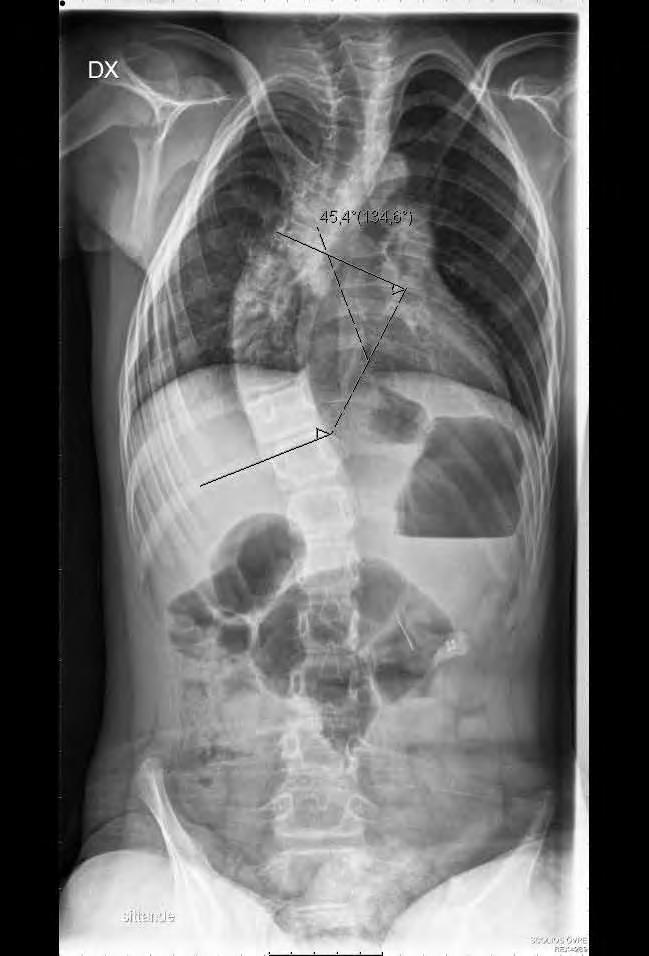

Neuromuskulära skolioser är ofta komplicerade och svåra att behandla. I allmänhet uppträder dessa ryggradsdeformiteter ganska tidigt, de blir snabbt stela och är progressiva. Ofta resulterar de i ett snedställt bäcken och kan också innefatta en svår sagittal inbalans som gör att de utgör ett stort hinder för normal funktion.

Av Acke Ohlin

Den kirurgiska behandlingen vid neuromuskulär skolios är den hittills enda kända metoden för att stoppa progress.

Skolios uppträder i ungefär hos var fjärde patient med CP. Ju mer spastisk patienten är, desto större är risken för svår deformitetsutveckling. Hos patienter med kvarstående gångfunktion är behandlingen ofta helt likartad den vid idiopatisk skolios. Patienter med CP har ofta längre tid för skoliosutveckling då deras skelettala mognad äger rum något senare än normalt. Vid skelettal mognad är risken för fortsatt progress 0,8 grader per år vid krökar som är mindre än 50 grader enligt Cobb och 1,4 grader när kröken överstiger 50 grader. Den goda effekten av Baklofen är observerad framför allt vid spasticitet i extremiteterna men det finns inte något säkert vetenskapligt stöd för dess effekt på utvecklingen av ryggradsdeformiteten även om det allmänna välbefinnandet blir bättre.

11-årig flicka med CP och spastisk tetrapares. Hon hade en extremt snabb skoliosutveckling från Cobb 45 grader till drygt 70 grader på tre månader. detta föranledde en snar op från Th2 till L5 med transpedikulära skruvar enl. Suk. Blödningen uppgick till 1500 ml. Postoperativt har vi inga restriktioner avseende mobiliseringen då så många fixationspunkter användes. Patienten hade postoperativt lunginflammation som dock snabbt svarade på antibiotikabehandling.

patisk skolios varför preoperativ tappning för autolog transfusion bör övervägas. Korrektion och fusion är ofta indicerade då

Cobbvinkeln är 40 – 60 grader. Vid CP är en bakre operationsmetod idag den vanligaste. Traditionellt har man använt sublaminär stag-

fixation med cerclage, en utveckling som Luque i Mexico utvecklade i slutet av 1970-talet. Idag används allt oftare transpedikulära skruvar enligt Suk från Sydkorea. Ett ständigt debattämne är när man ska inkludera bäckenet i instrumenteringen. Ett snedställt bäcken över 20 grader brukar ofta anges som indikation för denna åtgärd. Bäckenet och dess ställning kan betraktas som en del av deformiteten som helhet och är linjen rak från L4 och ner till bäckenet kan man enligt egen erfarenhet ofta stanna vid L5 och förlita sig på den ofta utomordentligt väl utvecklade iliolumbala ligamentapparaten. Vid operationen brukar instrumenteringen sträcka sig från övre bröstryggen (Th 1 – Th 2) till L5 eller bäckenet. I de mest krökta delarna av ryggen gör man ofta multipla bakre lösningar. Det går till så att man gör fenestreringar intill epiduralrummet och resecerar intervertebrallederna. Vanligtvis sätter vi skruvar i samtliga tillgängliga pediklar för att fördela lasterna under själva korrektionen så man inte riskerar en tidig skruvlossning (pull out). I rigida fall använder vi oss av reduktionsskruvar som har en förlängning av skruvarnas gängor, man fördelar då krafterna till många skruvar under korrektionsfasen. När korrektionen är färdig biter man av skruvhuvudsförlängningarna. Stagtjockleken ska vara så stor som patientens konstitution tillåter, framförallt för att få en bättre korrektion men också för att minska risken för stagbrott. Ibland använder vi ett grövre stag på korrektionssidan, den konkava och djupare belägna sidan och ett med mindre diameter på den konvexa sidan där implantaten ligger mer ytligt.